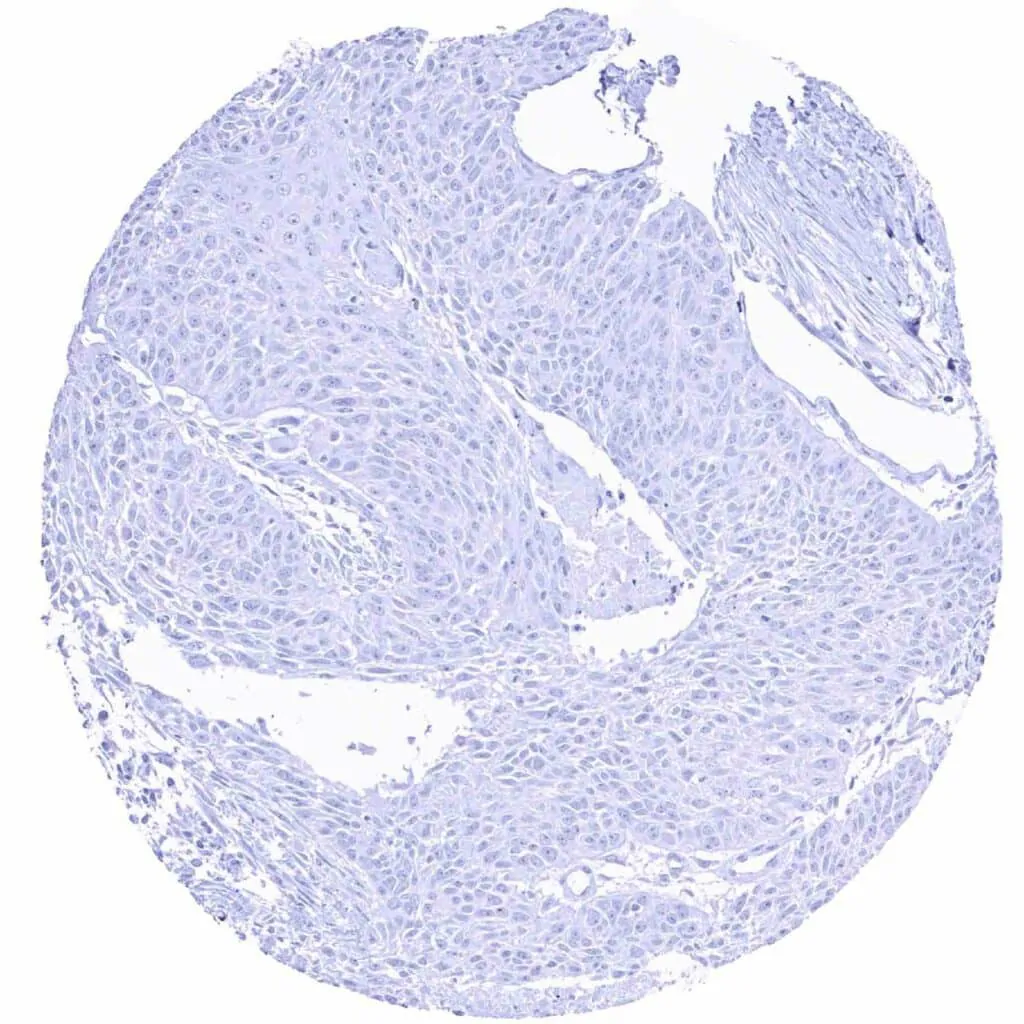

Esophagus – MYH7 negative squamous cell carcinoma